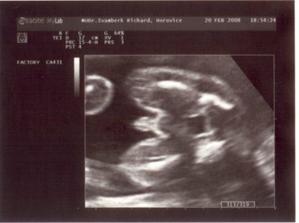

Jako v pohádce. 1.9.2007 jsme měli svatbu. 18.9.2007 jsme odjeli do Egypta na svatební cestu. Ze které jsme přijeli ve třech. Opravdu se nám to povedlo. 7.10.2007 jsem nedostala MS 10.10.2007 HURÁ !!!! Těhoteský test pozitivní. 12.11.2007 první KO, jsem 9+1 tt. Pan doktor mi dělal UTZ, dal mi první fotku mimíška. Těhotenství potvrzeno na 100 %,dostala jsem Těhotenskou průkazku. 29.11.2007 11+6 tt Byla jsem na odběru krve. Mám nízký tlak. 10.12.2007 13+3 tt KO viděla jsme opět mimíško na UTZ, má se čile k světu. Krev je vpořádku. 13.12.2007 potvrzení od obvodní lékařky a měření EKG. 3.1.2008 16+4 tt KO odběr krve na Triple test. UTZ mimíšku pěkně bije srdíško. Mám stále nízký tlak. Berou mě křeče do lýtek a pálí žáha. Pan doktor mi napsal MagneB6. 19.1.2008 18+6 tt už se pomalu do ničeho nevejdu. První nákup těhu kalhot a těhu blůza. 22.1.2008 19+2 tt dnes ráno jsme cítila jak mě mimíško několikrát koplo. A dopoledne v práci jsem cítila takové šimrání v bříšku. 28.1.2008 dneska jsem koupila mimíškovi první bodíčka. 31.1.2008 20+4 tt KO Trile test nagativní. Pan doktor mi dělal UTZ a pravděpodobně to bude KLUK. Poznala jsme to i já. Mimíško už váží 400g. Manžel měl radost. 4.2.2008 21+1 tt první těhotenské plavání. Bylo to moc pěkné a myslím, že i mimíšku v bříšku se to líbilo. 9.2.2008 – 16.2.2008 mám dovču. Jeli jsme na hory, ale já jsme raději nelyžovala, abych neublížila mimíšku. Vynahradím si to až příští rok. Hodně jsem odpočívala a chodila na procházky. 18.2.2008 kontrola u zubaře. Vše v pořádku. 19.2.2008 v práci mi bneska hodně tvrdlo a bolelo břicho. Tak uvidím jak mi bude zítra. 20.2.2008 23+3 tt opět mě tvrdlo a bolelo břicho až do zad. A docela intenzivně. Popráci jsem šla rovnou k doktoru. Vyšetřil mě a říkal, že to není moc dobré. Raději mi napsal neschopenku. 21.2.2008 bolí mě v kříži, především při chůzi. Jen doufám, že to nebude až do konce těhulkování. 27.2.2008 24+3 tt dneska jsem šla k obvodní doktorce s tou bolavou kyčlí. Stále mě dost bolí. Poslala mě na těhotenské cvičení, kde mi ukážou nějaké uvolňovací cviky a mám odpočívat. Snad to přejde. 5.3.2008 25+3 tt těhotenaké cvičení v nemocnici. Sestřička mi ukázala nějaké cviky na uvolnění kyčle a masáž. 10.3.2008 26+1 tt dneska jsme byli s manželem na 4 D UTZ. Bylo to moc hezké, mimíško se nám hezky ukázalo. Dokonce jsme viděli, že je to opravdu kluk. Pan doktor nám udělal nějaké fotky a nahrál mimíško na DVD. Je to opravdu moc krásný a jedinečný zážitek. 11.3.2008 26+2 tt dnes jsem byla v nemocnici na testu na cukrovku. 13.3.2008 začala jsme chodit do Solné jeskyně. Moc pěkně se tam relaxuje. Rozhodně to všem doporučuji. 19.3.2008 Dnes velký nákub oblečků na mimíško. 20.3.2008 27+4 tt KO test na cukr mám v normě. Tlak stále nízký a žáha mě pořád pálí. Bolest kyčle už ustoupila. Parvděpodobně mimíško změnilo polohu a netlačí už na nic. 29.3.2008 Byli jsme se podívat na kočárek. Nakonec se nám nejvíce líbí kočárek JANE SLALOM PRO, barva hnědooranžová. 10.4.2008 začala jsme chodit na těhu cvičení na Gymbalonech. 16.4.2008 první hodina předporodní přípravy. 17.4.2008 31+4 tt KO UTZ mimíško podle měření už váží 2100g, doufám, že to nebude žádný obřík. Jinak se má k světu a vše je v pořádku. Byla mi odebrána krev. 25.4.2008 32+5 tt pěkně mě bolí v krku. Návštěva obvodní lékařky. Udělala mi výtěr a uvidí podle výsledků. 28.4.2008 výtěr je vpořádku, ještě mě pro jistotu poslala na krční. Prý v těhotenství bývají zduřelé krční mandle. Tak by to mělo přejít samo. Mám brát pouze těhu vitamíny. Dneska jsme si přivezli kočárek. Nechali jsme ho u rodičů, pro jistotu, pověra je pověra, ale kdo ví. 4.5.2008 34 tt nástup na mateřskou dovolenou. Začínám s masáží hráze. 5.5.2008 34+1 tt KO UTZ mimíško už tam nemá moc místa, váží už 2500g, Mám nízké hodnoty železa v krvi. Tak jsem dostala vitamín železo. Magnesium už nemám brát. Dneska jsme byli s manželem v nemocnici, kde budu rodit, na předporodní besedě. Řekli nám, co nás čeká při porodu, a ukázali porodní pokoj. 8.5.2008 doma generální úklid a příprava na mimíško. Oblečky na mimíško mi pere a žehlí mamka, je moc hodná a hodně mi s tím pomáhá. Jsem moc ráda a tato práce mi odpadla a já si domů odvezu už vše hotové. 9.5.2008 34+5 tt celou noc jsem nespala, mám rýmu a strašný kašel. Docela se bojím i o mimíško. Tak jsem raději šla k obvodní doktorce. Ta mě poslechla, mám zánět průdušek. Dala mi antibiotika ZINNAT 250mg. Moc nejsem nadšená. Ujišťovala mě, že se můžou v těhotenství, a i v lékárně mi to říkali. Doma jsem si to našla i na Internetu. Tak snad bude vše vpořádku. 12.5.2008 35+1 tt Dneska jsem byla na natočení na EKG, to prý potřebuji k porodu. 13.5.2008 Opět mě začal bolet kyčel, jak mě již jednou bolel. Asi se mimíško nějak jinak uvelebuje a tlačí mi na nějaký nerv. 15.5.2008 35+4 tt KO doktor říkal, že mě ta kyčel pravděpodobně přestane bolet až po po porodu. Tak nejsem moc šťastná, protože je to dost omezující, především při chůzi. Mimíško je vpořádku. Dneska mi poprvé natáčel monitor, tak jsem slyšela tlukot mimíškova srdíčka. 26.5.2008 37+1 tt Dneska mám narozeniny!!! KO pan doktor mi dělal vyšetření a kultivaci z pochvy. Od příštího týdne už budu chodit na KO do nemocnice, kde také budu rodit. Tak už jsme se rozloučili a mám k němu přijít na KO až po šestinedělí. Snažím se, co nejvíce odpočívat. 2.6.2008 38+1 tt KO už v nemocnici. Výsledky kultivace nejsou moc dobré, tak jsem dostala globule na zavádění. S paní doktorkou jsme se domlouvali na průběhu porodu, protože jsem v minulosti měla zlomenou sedací kost. Domluvili jsme se, že porod necháme přírodní cestou a pokuď bude něco špatně, tak přistoupí k císařskému řezu. Doufám, že bude vše bez komplikací. Opět mi natáčeli monitor. 9.6.2008 39+1 tt KO natáčení monitoru. Je moc hezké slyšet jak mimíšku bije srdíčko. Dneska mi dělala vyšetření, vše je vpořáku. Zítra jdu na UTZ. 10.6.2008 39+2 tt dneska jsem byla na UTZ, kde měřili mimíško. Podle měření váží asi 3509g. Nakonec jsme se s paní doktorkou domluvili, že pokud neporodím do 22.6., tak si v pondělí 23.6. v 8 hodin půjdu lehnout do nemocnice, abych moc dlouho nepřenášela a mimíško nebylo moc velké, vzhledem k té zlomené sedací kosti. No nějak mi to těhulkování moc rychle uteklo a už se ten obávaný porod opravdu blíží, což si nějak moc nechci připouštět. Ale můžu říci, že jsem si to moc užila a ještě užívám. Je to asi opravdu ta nejkrásnější doba v mém životě. Vědět, že v sobě máte mimíško, a těšit se na něj. 16.6.2008 40+1 tt tak dneska už jsme byla na natočení monitoru a na poslední KO. Doktorka mi dělala vyšetření a říkala jak miminko je hezky sestouplé. Prý je dobře připraveno k porodu a vše vypadá, že bych mohla porodit dříve než v pondělí. Aby mi nemuseli porod vyvolávat. Já bych raději chtěla porodit normálně bez vyvolání. Doufám, že se to povede. Jinak v pondělí 23.6.2008 nastupuji do nemocnice. No tak musíme doma zkusit osvědčené babské rady, snad se nám to povede. Mimíško se nějak v bříšku zabydlelo a vůbec se mu nechce ven. Držte nám palečky. Děkujeme. 17.6.2008 40+2 tt od 23.00 hod tvrdnutí bříška, že by to již bylo ono???? Ve 23.43 hod začínají kontrakce po 10 minutách. 18.6.2008 40+3 tt ve 2.30 hod odjezd do porodnice. Kontrakce po 4,5 minutách. V 8.29 hodin DAVÍDEK na světě. Váží 3880g a měří 52 cm. Tatínek byl u porodu a byl moc velkou oporou mamince. Moc si toho vážím. Je to velká odměna a stálo to za to. Těď už jsem ne dva, ale tři. Jedna velká rodina. Jsme moc šťastni.